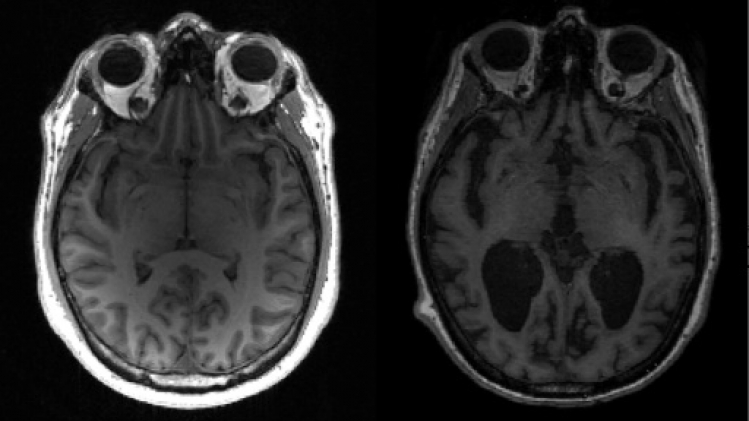

On connaît deux grands mécanismes, sans bien comprendre leur interaction: la formation dans le cerveau de plaques de protéines dites amyloïdes, qui compriment les neurones et les détruisent à terme. Et l'accumulation d'autres protéines, dites Tau, au sein des neurones eux-mêmes.

Des examens existent déjà: via une ponction lombaire ou via une technique d'imagerie médicale, la tomographie par émission de positons (PET). Mais comme ils sont longs, lourds et coûteux, beaucoup de patients en restent bloqués à des constats cliniques, telle une forte perte de mémoire.